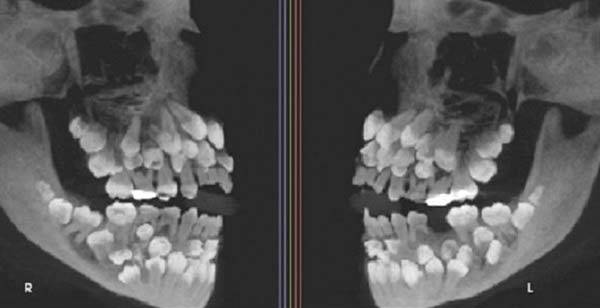

11세 소녀 입 속에 ‘이것’ 81개가… 엑스레이 사진 보니 ‘충격적’

브라질의 한 11세 소녀 입안에서 무려 81개의 치아가 발견돼 학계의 주목을 받고 있다.

17일(현지시각) 베트남 VN익스프레스 등 외신에 따르면, 브라질 미나스제라이스주에 사는 소녀는 유치 한 개를 빼기 위해 병원을 찾았다가 엑스레이 검사 중 총 81개의 치아가 있다는 사실이 확인됐다. 유치 18개, 영구치 32개, 과잉치 31개였다. 소녀를 진료한 주이스지포라 연방대 치과병원 연구진은 “이런 상태는 ‘다발성 과잉치증’”이라며 “보통은 한두 개의 과잉치만 생기는데, 30개 이상 발견된 사례는 전 세계적으로도 매우 드물다”고 말했다.

연구팀은 정밀 영상 촬영으로 치아 위치를 확인하고, 유전적 원인을 찾기 위해 유전자 검사도 병행했다. 일반적으로 다발성 과잉치는 선천성 유전질환인 쇄골두개이형성증(쇄골·두개골 발달 이상), 가드너 증후군(유전성 대장 질환), 구개열(입천장이 갈라진 증상) 등과 함께 나타나는 경우가 많다. 하지만 이 소녀에게서는 해당 질환이 발견되지 않았다.

다만, 유전학적 검사 결과 9번 염색체 일부 구간의 배열이 바뀐 ‘염색체 역위’가 확인됐다. 연구진은 “이 유전적 변이가 과잉치 발생에 영향을 미쳤는지는 아직 명확하지 않다”고 했다.

과잉치는 일반적인 치아 수를 초과해 추가로 자라는 치아를 말한다. 유아기에는 20개, 성인기에는 32개가 정상이다. 과잉치는 잇몸 속에 숨어 있거나 겹쳐 나오는 경우가 많아 다른 치아를 밀어내거나 치열을 흐트러뜨릴 수 있다. 여러 개의 과잉치가 존재할 경우 턱관절 통증, 인접 치아 손상 등의 문제도 동반될 수 있다.